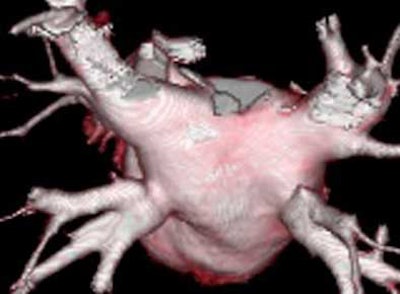

![]() |

| Above, volume-rendered MDCT epicardial view of atrium depicts four pulmonary veins: right superior (RS), right inferior (RI), left superior (LS), left inferior (LI). Image courtesy of Dr. Joan Lacomis. |

What does the electrophysiologist need? "What our electrophysiologists really like to see are extra-atrial or so-called epicardial and endoatrial, endocardial, volume-rendered views -- so we can really show them the three-dimensional anatomy," Lacomis said. "But they don't want to see the whole heart. They want to see only the left atrium, the left atrial appendages, and the distal pulmonary vein. The segmentation algorithms available on the workstations are helping to exclude some of the other adjacent anatomy, and are quite helpful in time-saving."

Epicardial volume-rendered views should include the left atrium and the distal third of the pulmonary veins, but not the heart, pulmonary arteries, aorta, or vena cavae, in order to show the relevant structures without their being obscured by the adjacent anatomy.

"On the posterior (epicardial) view you can see clearly four pulmonary veins on this patient," she said. "We can look for ostial branches (defined as branches that join the main pulmonary trunk within 5 mm of the AV junction). And as we rotate this left atrium around, we really get a good feel for local LA size and shape."